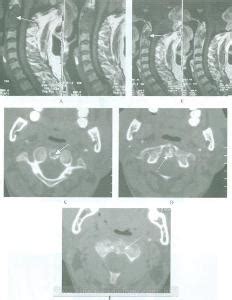

许莫氏结节是椎体的软骨板破裂,髓核可经裂隙突入椎体内,造成椎体内出现半圆形缺损阴影。

L5/S1椎间盘向左后方突出,S1椎体左后上缘许莫氏结节形成。